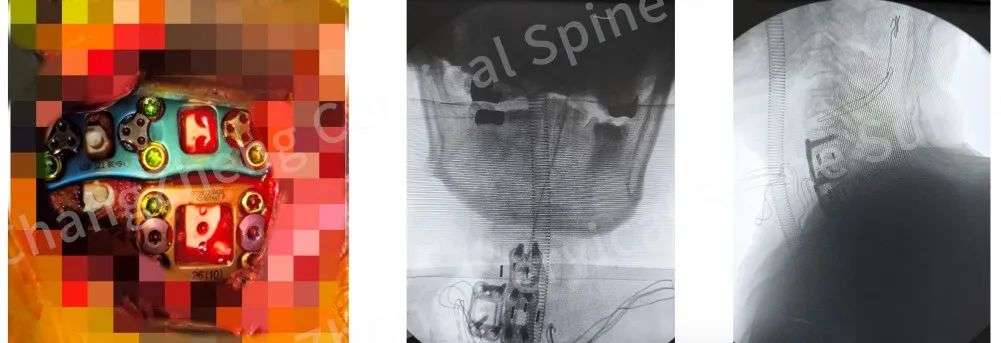

陈华江教授、王新伟教授与麻醉科团队紧密协同完成手术

手术台上,陈华江教授、王新伟教授与麻醉科王成才教授、傅海龙教授、羊海琴护士长带领的精锐麻醉护理团队紧密协同,如同在刀尖上起舞。

尤为关键的是,团队创新性地应用了“卫星钢板”固定技术,在常规固定之外巧妙增加辅助钢板,为重建的颈椎提供了前所未有的超强稳定性,这一技术应用在此类极端病例中尚属首创。

团队创新性应用“卫星钢板”固定技术,为重建的颈椎提供了前所未有的超强稳定性